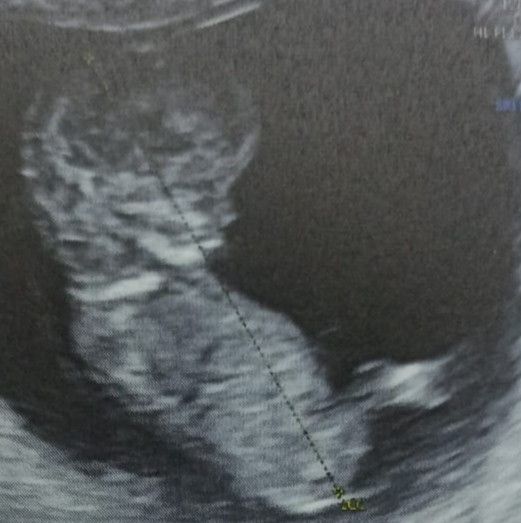

Привет, у меня сегодня 10 нед и 2 дня. Делала УЗИ. Токсикоз сохраняется, подташнивает, в течение дня. Гевискон облегчает состояние. Вот и фотография как наши малыши выглядят на таком сроке